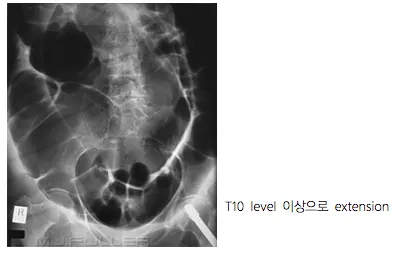

D2. Imaging

(1) Simple film : Abd S/E, Chest PA, Lat. decubitus (greatest volue : free air detection)